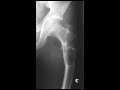

Unicameral bone cyst

This is a case of a 9 year old girl who presented with hip pain. Frontal and lateral radiographs of the hip demonstrates a bubbly, expansile lytic lesion within the proximal femur. There is no evidence of a matrix. The lesion is well defined, with a so called narrow zone of transition. No pathologic fracture is demonstrated radiographically. There is no periosteal reaction or a soft tissue component. Due to the pain the patient was experiencing, she want on to surgical biopsy and curretage. Pathology demonstrates a simple bone cyst, also known as a unicameral bone cyst. The radiographic appearance correlates well with the pathology. Additional differential consideration given the patient age and appearance of the lesion would include aneurysmal bone cyst as well as monostotic fibrous dysplasia. When pathologic fracture of a simple bone cyst occurs, a "fallen fragment sign" can be seen. This sign has high specificity but poor sensitivity.